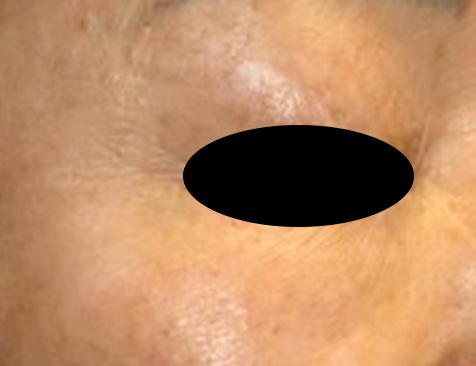

인라이튼 니플스 눈가 잔주름 제거 사례

제가 사용하는 인라이튼 니플스로 눈가 잔주름을 개선한 사례입니다.

시술 전, 후를 비교해보면 눈가 잔주름이 정리되면서 피부 텍스처도 훨씬 매끄러워진 것을 볼 수 있는데요.

위 사례는 제조사에서 제공한 사례라 정확한 시술 횟수가 표기되어 있지 않지만 이런 효과가 1회에 바로 나타나는 것이 아니라 여러 차례 반복 시술을 필요로 합니다.